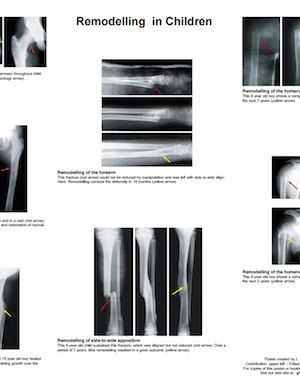

Remodelling Of Fractures In Children Staheli L.. Poster. 18" x 24". 2004. GHO Publication. See Available Translations Details An easy-to-read poster with examples of fracture remodeling of the major long bones in children. Languages View or Download (PDF) [Chinese] ISBN #978-1-60189-146-4 [2 MB] View or Download (PDF) [English] ISBN #978-1-60189-020-7 [200 KB] View or Download (PDF) [Spanish] ISBN #978-1-60189-105-1 [600 KB] Translators Chinese translation by Lin Feng. Spanish translation by Julio Nuñez Tapia. Need a PDF reader? Click the icon to get Adobe's free one. For best results, "Right-Click / Save-As" PDF links.